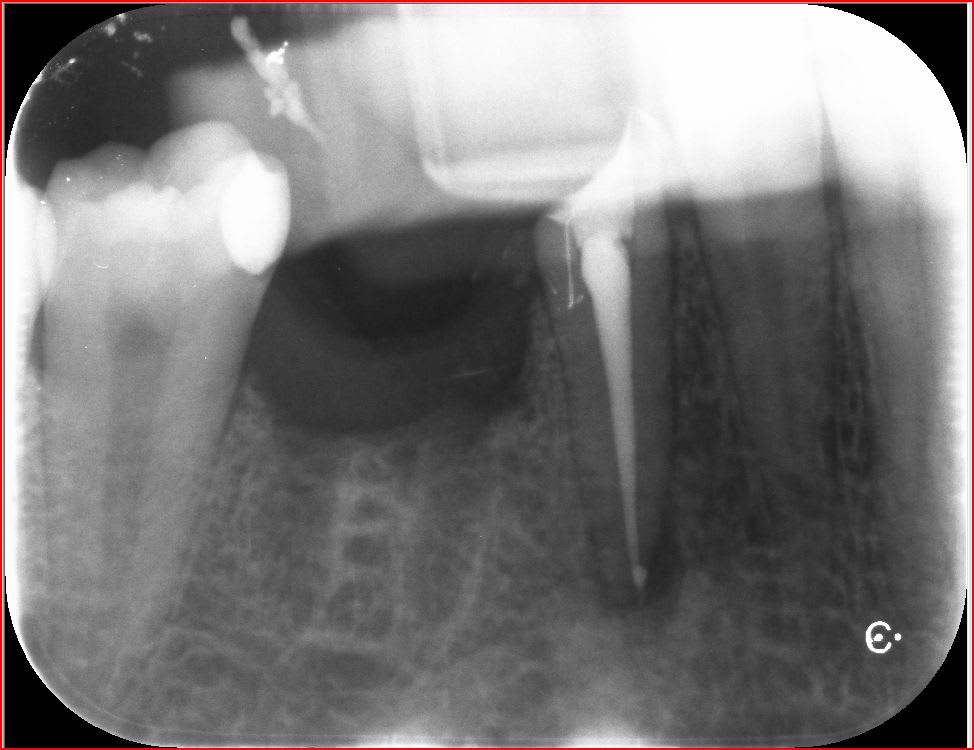

C'est la pulpe c'est la pulpe.

Putain j'ai eu chaud. -) vestibulaire ? Lingual ? vestibulaire lingual ?........Lingual !

Capture d écran 2017 02 20 16.51 - Eugenol

Capture d écran 2017 02 20 17.06 - Eugenol

Il y a un truc bizarre, sur tes RX on a l'impression que l'orifice du canal est distalisé,un peu comme la lésion apicale et ton obturation et plus dans l'axe, un artefact probablement.